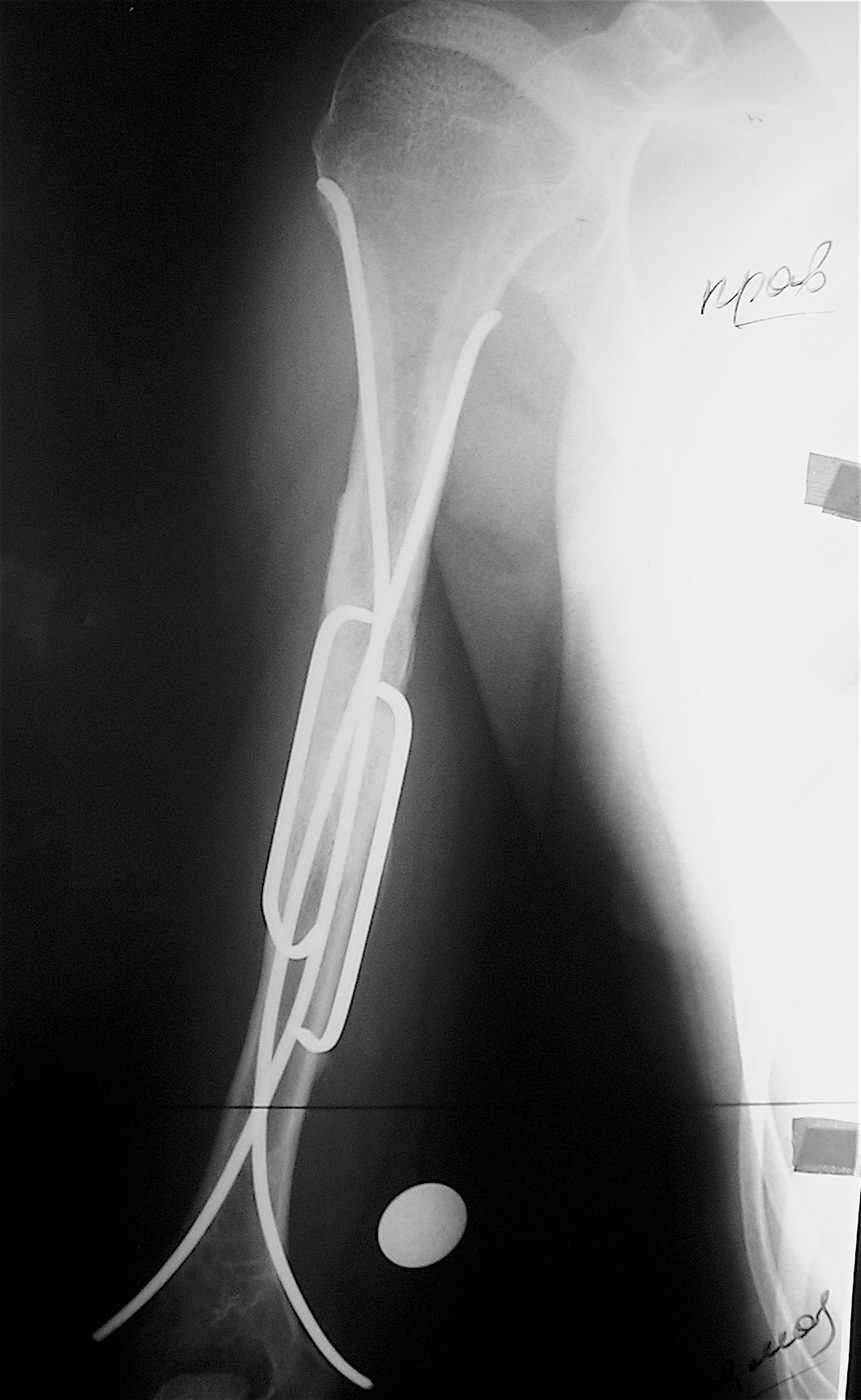

Закрытый, патологический перелом в с/з правой плечевой кости на фоне аневризмальной кисты диафиза правой плечевой кости.

Выполнена операция: экскохлеация кисты, остеосинтез титановыми эластичными стержнями и металлической скобой, аллопластика патологического очага материалом «Лиопласт».

Функция конечности сохранена, ребенок себя обслуживает.

Имеется укорочение правой верхней конечности  на 1,5 см за счет плеча.